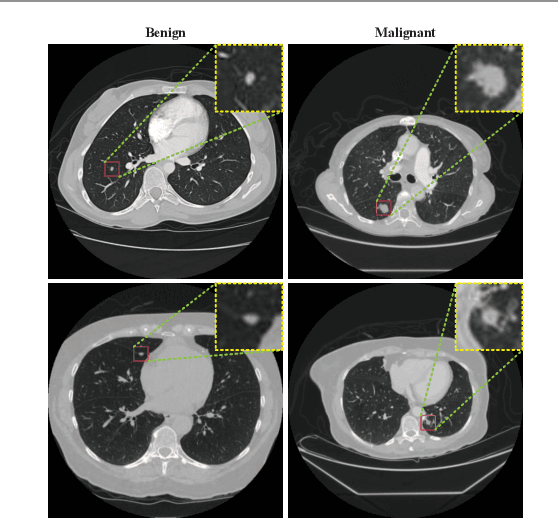

Abstract:Background and Objective:Computer-aided diagnosis (CAD) systems promote diagnosis effectiveness and alleviate pressure of radiologists. A CAD system for lung cancer diagnosis includes nodule candidate detection and nodule malignancy evaluation. Recently, deep learning-based pulmonary nodule detection has reached satisfactory performance ready for clinical application. However, deep learning-based nodule malignancy evaluation depends on heuristic inference from low-dose computed tomography volume to malignant probability, which lacks clinical cognition. Methods:In this paper, we propose a joint radiology analysis and malignancy evaluation network (R2MNet) to evaluate the pulmonary nodule malignancy via radiology characteristics analysis. Radiological features are extracted as channel descriptor to highlight specific regions of the input volume that are critical for nodule malignancy evaluation. In addition, for model explanations, we propose channel-dependent activation mapping to visualize the features and shed light on the decision process of deep neural network. Results:Experimental results on the LIDC-IDRI dataset demonstrate that the proposed method achieved area under curve of 96.27% on nodule radiology analysis and AUC of 97.52% on nodule malignancy evaluation. In addition, explanations of CDAM features proved that the shape and density of nodule regions were two critical factors that influence a nodule to be inferred as malignant, which conforms with the diagnosis cognition of experienced radiologists. Conclusion:Incorporating radiology analysis with nodule malignant evaluation, the network inference process conforms to the diagnostic procedure of radiologists and increases the confidence of evaluation results. Besides, model interpretation with CDAM features shed light on the regions which DNNs focus on when they estimate nodule malignancy probabilities.